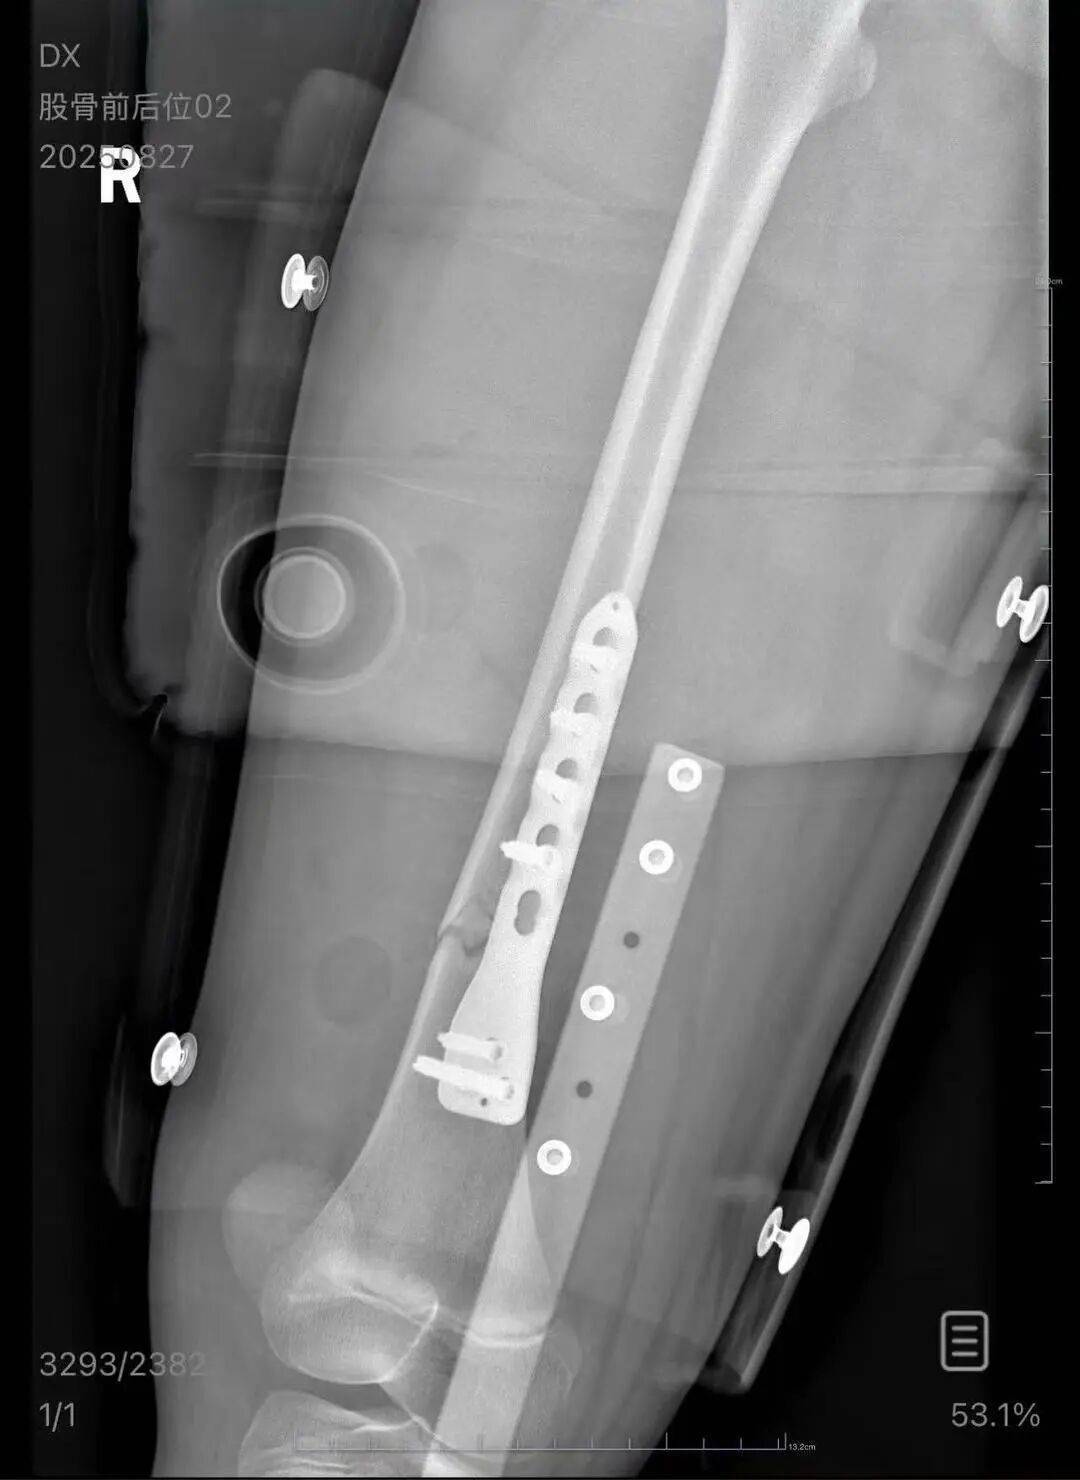

▲朱女士女儿手术后拍的X光片 受访者供图

朱女士向记者出示的医院病历显示,8月24日凌晨,朱女士的女儿到医院就诊。医院诊断朱女士的女儿右股骨骨折,需要住院进一步治疗。

朱女士称,自己是离异状态,为了照顾小孩请假在家,也没有经济来源。“现在孩子的医药费用已经花了5万多,后期还要进行康复治疗,我的压力非常大。”“医生说孩子还小,恢复快,钢板固定后很难恢复如初,甚至可能会出现长短腿的现象。”